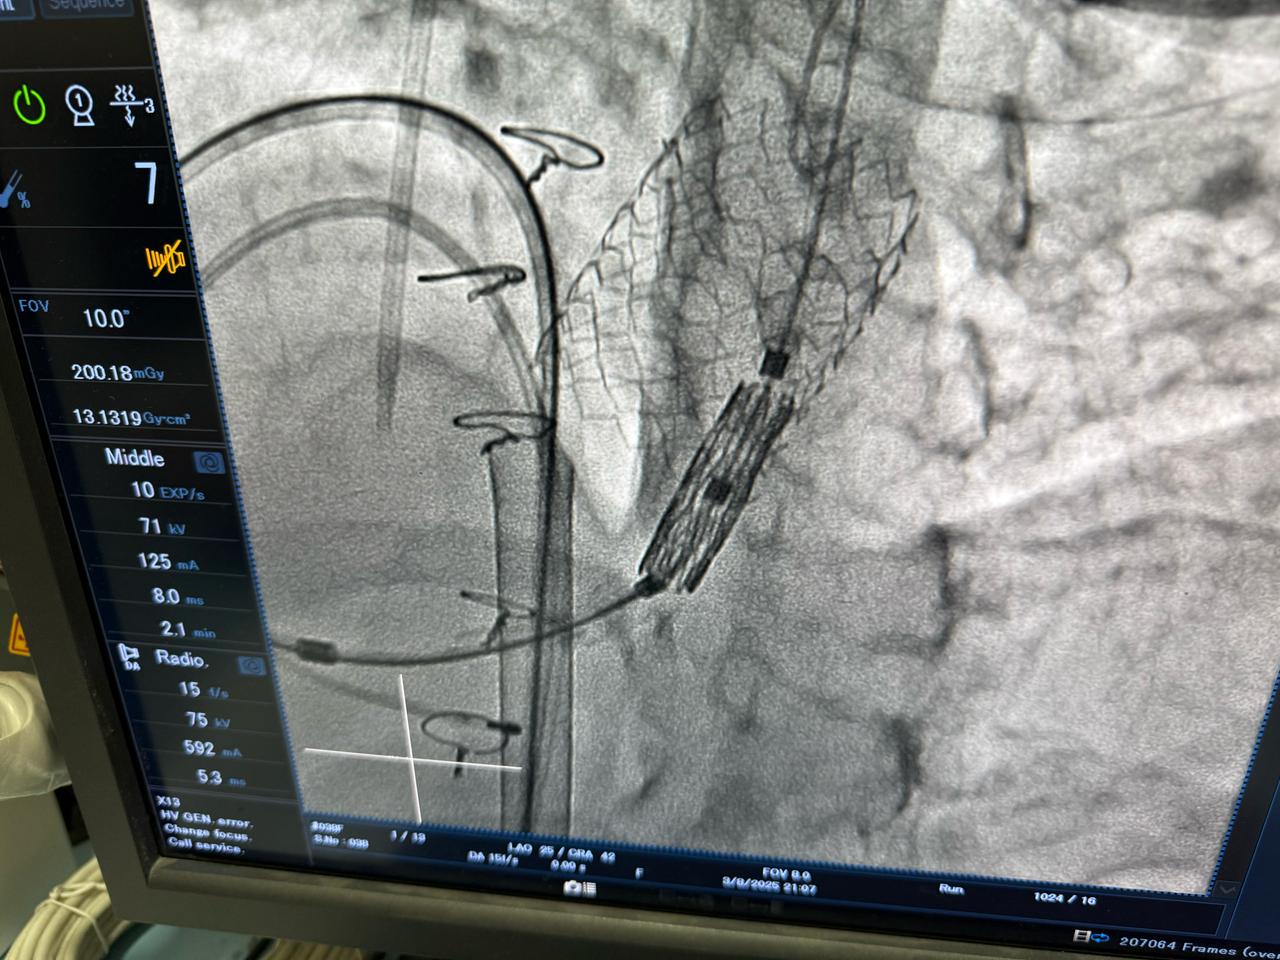

أعلنت وزارة الصحة والسكان عن نجاح عملية دقيقة لتغيير الصمام الرئوي بالقسطرة لشابة تبلغ من العمر 23 عامًا، كانت تعاني من ارتجاع شديد بالصمام الرئوي نتيجة جراحة رباعي فالوت السابقة، وهو أحد أكثر العيوب الخلقية القلبية تعقيدًا.

وصرّح الدكتور حسام عبد الغفار، المتحدث الرسمي لوزارة الصحة والسكان، بأن العملية أُجريت باستخدام أحدث التقنيات العالمية داخل أكاديمية قلب المبرة، التابعة للمؤسسة العلاجية، على يد نخبة من الخبراء المصريين، مؤكدًا أن هذا الإجراء الطبي المتقدم، الذي تجاوزت تكلفته مليون جنيه، يعكس قدرة الفرق الطبية المصرية على تنفيذ أدق التدخلات القلبية وفق أعلى المعايير الدولية.

وجرت العملية تحت إشراف الدكتور محمد إبراهيم شقوير، رئيس المؤسسة العلاجية، والدكتور هشام الفخراني، مدير مستشفى مبرة مصر القديمة، وبقيادة فريق طبي متخصص برئاسة الدكتور محمد صبري، رئيس قسم القلب، والدكتور أحمد السواح، مدير وحدة القسطرة، والدكتور علي جلال، مدير وحدة الأمراض الخلقية.